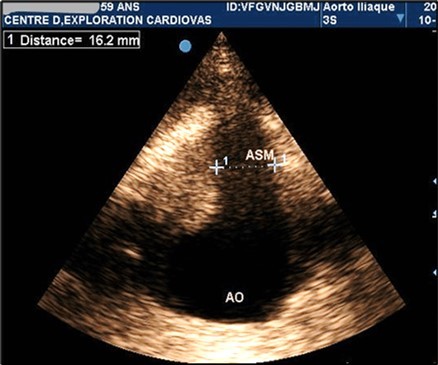

AAAs were fusiform in 23 patients (71.9%). The saccular aneurysm was present in 9 patients (28.1%). Figure 1 and (Figure 2).

Figure 1.Partially thrombosed 5.2cm fusiform suprarenal AAA with extension to the superior mesenteric artery in a 59-year-old subject (CEC 'Saint-Esprit' of the AMP-MCV).

Figure 2.Partially thrombosed 5.2cm fusiform suprarenal AAA with extension to the superior mesenteric artery in a 59-year-old subject (CEC 'Saint-Esprit' of the AMP-MCV).